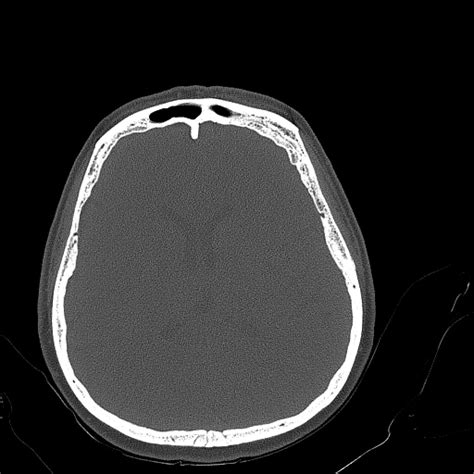

Hyperostosis frontalis interna (HFI) is a condition characterized by a benign, symmetrical thickening of the inner table of the frontal bone of the skull. While the term might sound intimidating, it is a relatively common radiological finding, often discovered incidentally during imaging scans performed for other reasons, such as headaches or minor head trauma. Understanding this condition is important for clinicians and patients alike, particularly because it can sometimes be associated with hormonal or metabolic factors, although its exact clinical significance remains a subject of ongoing research.

At its core, Hyperostosis frontalis interna manifests as bony growths—known as osteomas or nodular projections—on the inner surface of the frontal bone. Unlike malignant skull conditions, these deposits are benign and generally do not extend into the brain tissue itself. They are most frequently identified through computed tomography (CT) scans or magnetic resonance imaging (MRI) of the head.

- Imaging: A CT scan is the gold standard for visualizing bone density and structure, making it the most effective tool for confirming HFI.

One of the most important aspects of identifying Hyperostosis frontalis interna is ensuring it is not confused with more serious bone or intracranial disorders. While HFI is harmless, other conditions may require intervention. Distinguishing between them involves evaluating the pattern of bone growth and the age of the patient.